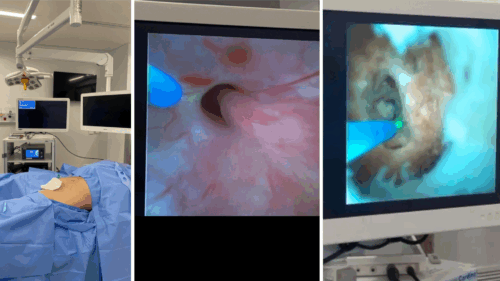

TÉCNICA MINIMAMENTE INVASIVA E ALTAMENTE EFICIENTE

A ureteroscopia flexível com laser de alta potência é um procedimento endoscópico, ou seja, realizado por dentro do corpo, sem necessidade de cortes externos. O aparelho flexível navega por todo o sistema coletor do rim, acessando a pedra diretamente através da uretra.

ETAPAS DO PROCEDIMENTO

O procedimento é realizado por via uretral, com introdução do aparelho até o rim. Uma bainha ureteral é usada para criar um canal de trabalho, por onde passam os instrumentos e o soro fisiológico usado na irrigação. Isso permite visualização constante durante a cirurgia.

“O tratamento do cálculo se inicia após esse acesso, com o uso do laser para fragmentação das pedras”, detalha o especialista.